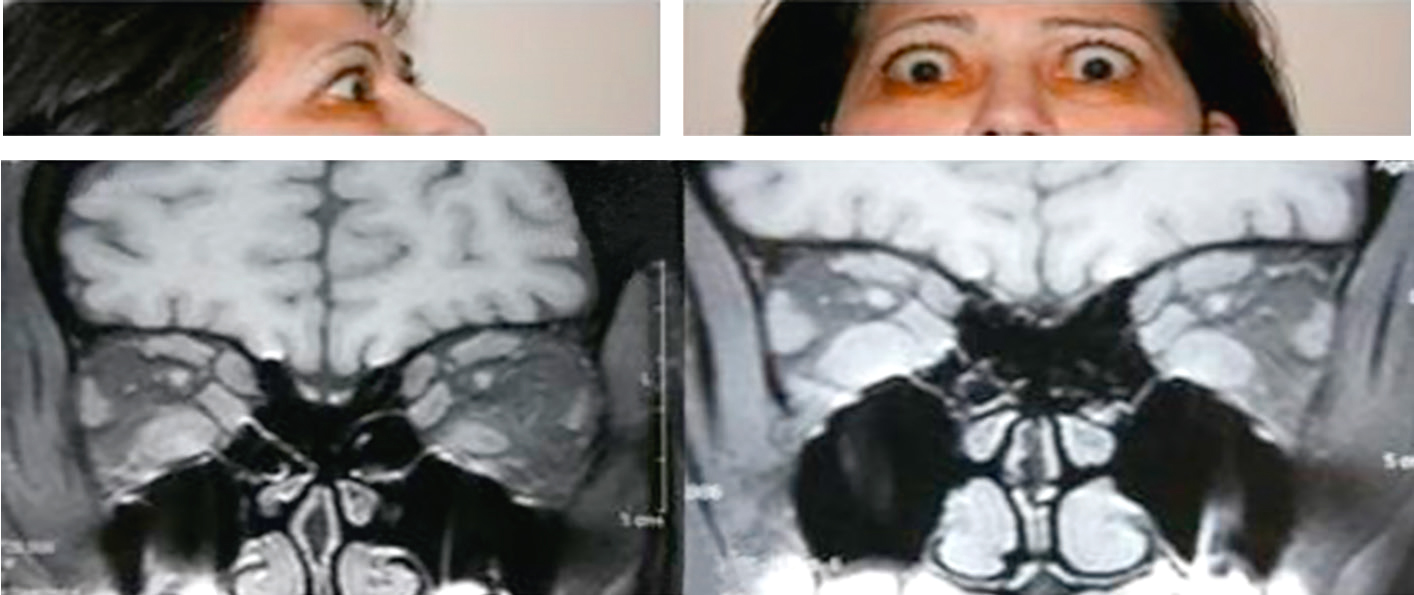

une orbitopathie de Basedow ou dysthyroïdienne (fig. 13.7) (voir item 242 : hyper-thyroïdie). Le tableau est en général bilatéral et s’accompagne le plus souvent d’une rétraction palpébrale. Le scanner ou l’IRM montrent une augmentation de volume des muscles orbitaires. Le diagnostic repose sur le bilan thyroïdien et surtout la présence d’autoanti-corps antirécepteurs à la TSH;

Fig. 13.7

Orbitopathie dysthyroïdienne.

La patiente présente une exophtalmie bilatérale avec rétraction des paupières supérieures. Le scanner en coupe coronale montre un épaississement des muscles extraoculaires, notamment des droits inférieurs.L'orbithopathie dysthyroïdienne, aussi appelée ophtalmopathie de Graves, est une maladie auto-immune liée à des troubles de la thyroïde, comme la maladie de Basedow-Graves. Elle affecte les tissus orbitaires autour des yeux, provoquant inflammation et gonflement. Les symptômes courants incluent des yeux exorbités (exophtalmie), vision double (diplopie), sécheresse oculaire, irritation, et parfois perte de vision. Les IRM montrent un épaississement des muscles extraoculaires et une augmentation du volume des tissus adipeux orbitaires, pouvant entraîner une compression du nerf optique et affecter la vision. Les traitements incluent des médicaments pour l'inflammation, des thérapies pour les symptômes oculaires, et parfois une intervention chirurgicale pour décompresser l'orbite ou corriger la position des yeux. La gestion de la fonction thyroïdienne est cruciale pour contrôler la progression de la maladie. L'orbithopathie dysthyroïdienne est une maladie complexe nécessitant une prise en charge multidisciplinaire.